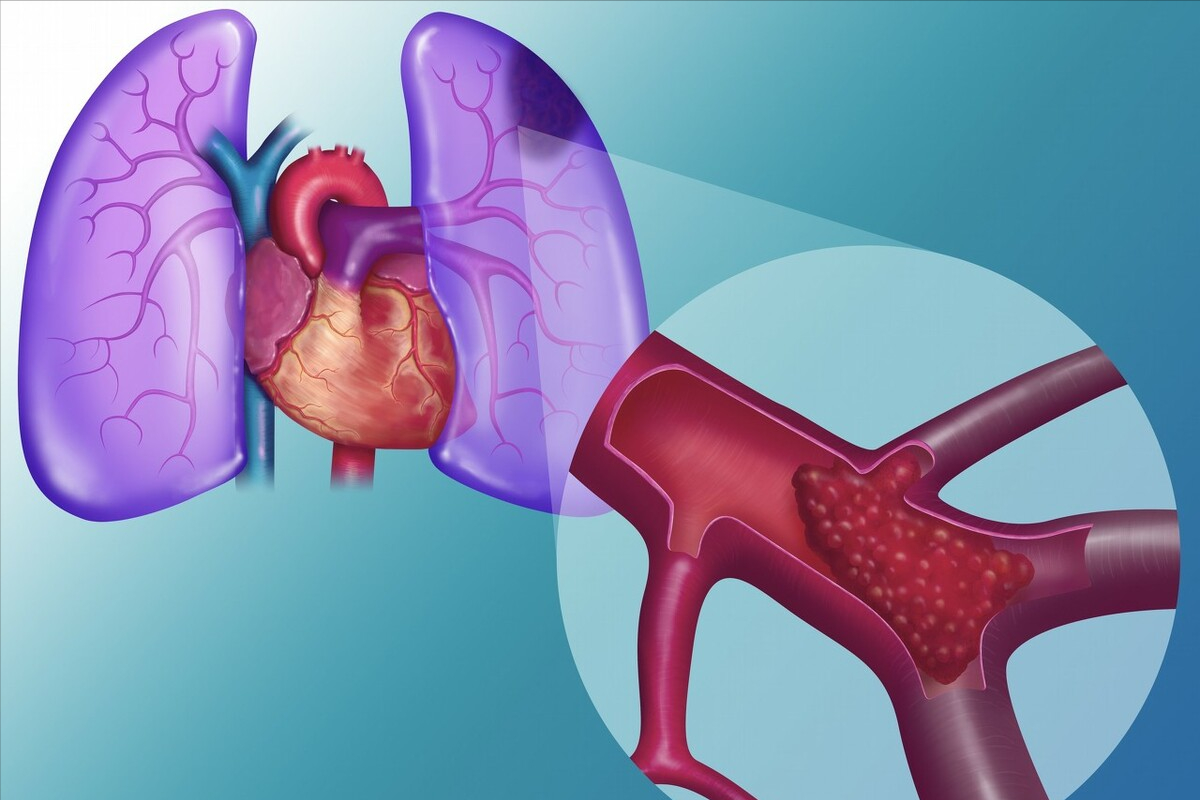

“肺栓塞是以各种栓子阻塞肺动脉或其分支的一组疾病或临床综合征的总称,会导致肺循环和呼吸功能障碍,小月在抽脂手术后出现血氧饱和度低等情况,再根据各项检查结果,基本可以判断是肺栓塞。若不及时调节,会导致严重的呼吸衰竭,严重者可能猝死,但如果能够尽早干预,预后还是比较好的。”浙大一院呼吸内科周华主任医师说。

一般来说,抽脂手术后发生肺栓塞,可能有两种原因:一是手术造成血管内皮损伤等原因,可导致深静脉血栓形成及肺动脉血栓栓塞的发生,为肺血栓栓塞;二是脂肪被抽吸后,由于脂肪细胞被破坏,脂肪细胞中的小颗粒有可能顺着破损的血管进入血液从而导致脂肪栓塞,为肺脂肪栓塞。这两种栓塞都可能在术后短时间内就发生。

两种原因造成的结果相似,但调节方案截然不同。根据小月的肺动脉CTA、肺部CT等检查结果显示,小月为肺脂肪栓塞,此时小月的肺部已是白茫茫一片,就像暴风雪一样,脂肪进入她肺部,刺激血管发生痉挛,产生严重的炎症因子风暴!